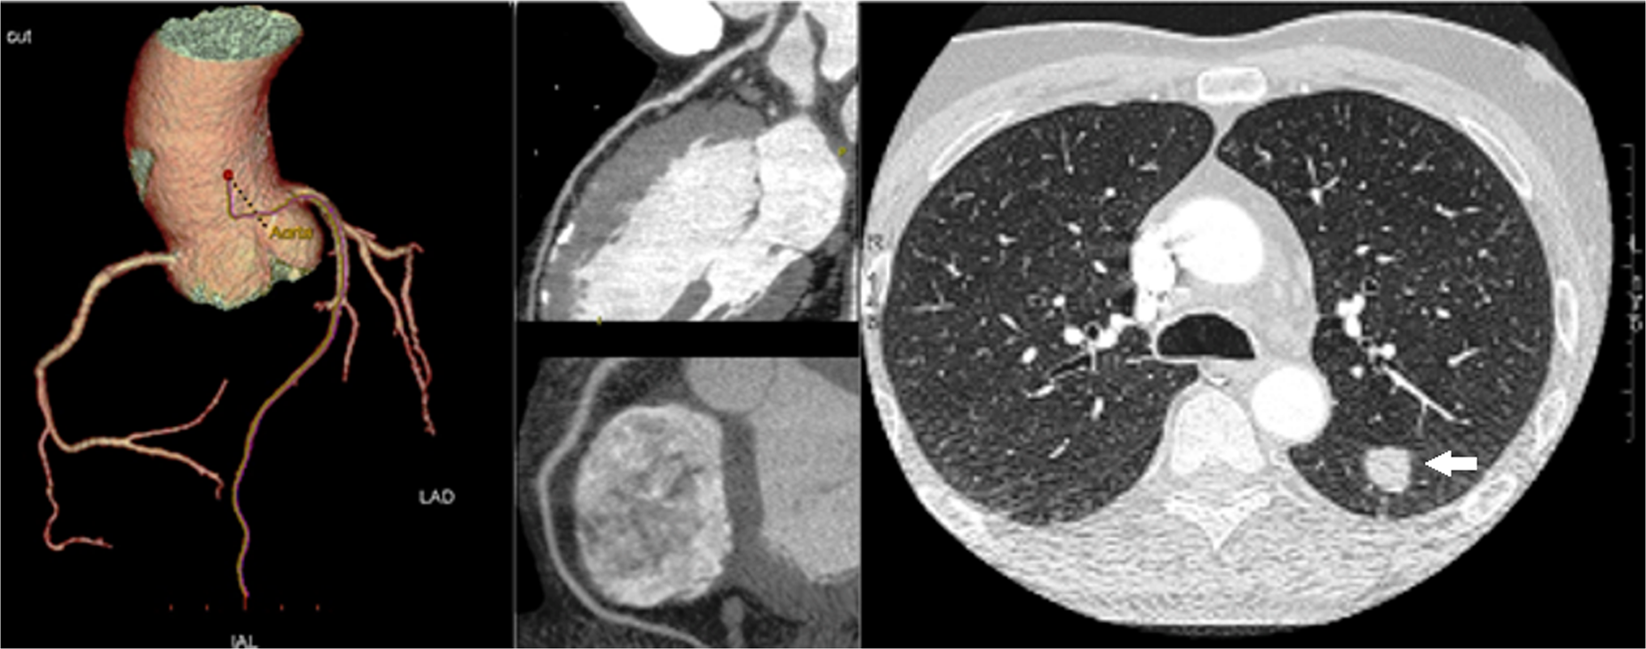

Figure 5

A case of coronary artery disease and lung cancer detection. CT images of the lungs showed a 20 mm pulmonary nodule (white arrow) in the left lobe (right panel). The patient underwent a complete diagnostic work-up, including positron emission tomography, and eventually underwent surgical resection. The cardiac CT revealed normal left coronary artery and right coronary artery (left panels).